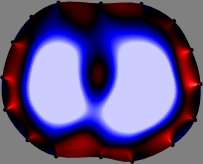

Figs. 3 and 4 compare the performance of the proposed FER method in (20) with the standard regularized least-squares method ((19) when \mathcal{R} is the identity matrix). The regularization parameter of the standard method was heuristically chosen for its best performance, and the parameter of the FER method was set to be one of three different values λ=0.05,0.2,𝜆0.050.2\lambda=0.05,0.2,\infty. The injection current was 1 mARMSRMS{}_{\tiny{\mbox{RMS}}} at 100 kHz, and the frame rate was 9 frames per second. The reference frame at t0subscript𝑡0t_{0} was obtained from the maximum expiration state. The measured data, 𝐕˙(tm)˙𝐕subscript𝑡𝑚\dot{\mathbf{V}}(t_{m}), represent the voltage differences between each time tmsubscript𝑡𝑚t_{m} and t0subscript𝑡0t_{0}. The blue regions, which denote where conductivity decreased by inhaled air, increased during inspiration and decreased during expiration. The FER method with λ=𝜆\lambda=\infty was clearly more robust than the standard method that produced more artifacts originated from the inversion process.

Figure 3: The reconstructed images of the conductivity change of the subject A by the standard regularized least square method and the proposed fidelity-embedded regularization (FER) method for three difference values λ=0.05,0.2,𝜆0.050.2\lambda=0.05,0.2,\infty. Here, the time step is 0.22 seconds (tm+2tm0.22subscript𝑡𝑚2subscript𝑡𝑚0.22t_{m+2}-t_{m}\approx 0.22).